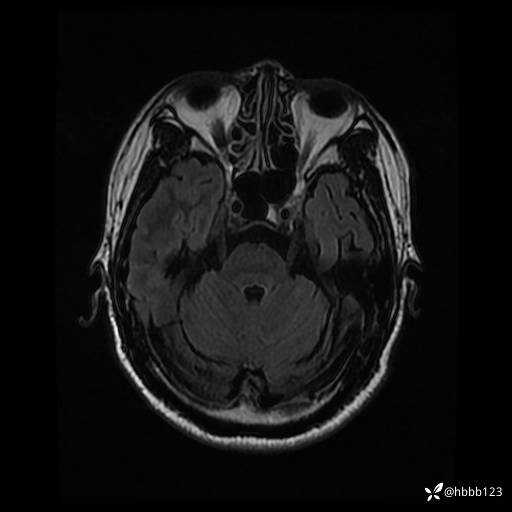

患者男,43岁。

简要病史:癫痫患者复诊,昨日发作5-6次,建议住院进一步治疗。

入院完善脑癫痫组合序列:

T2 Flair: